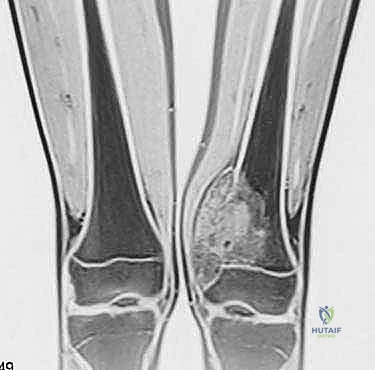

- الرنين المغناطيسي (MRI): هو المعيار الذهبي (Gold Standard) لتقييم الأورام. يوضح بدقة امتداد الورم في النخاع العظمي والأنسجة الرخوة، وعلاقته بالأعصاب والأوعية الدموية.

الحالة الأولى: إنقاذ ركبة رياضي شاب

شاب يبلغ من العمر 19 عاماً عانى من ألم مستمر في الركبة وتورم لم يستجب للمسكنات. بعد الفحص السريري الدقيق وإجراء الرنين المغناطيسي، اشتبه الأستاذ الدكتور محمد هطيف بوجود ورم. تم إجراء خزعة إبرة أساسية دقيقة جداً. أظهرت النتائج وجود "ساركوما عظمية" في مراحلها الأولى. بفضل الخزعة الدقيقة التي لم تلوث الأنسجة المحيطة، تمكن الدكتور هطيف لاحقاً من استئصال الورم بالكامل وتركيب مفصل صناعي خاص بالأورام، مما أنقذ ساق الشاب من البتر ومكنه من العودة للمشي بشكل طبيعي.